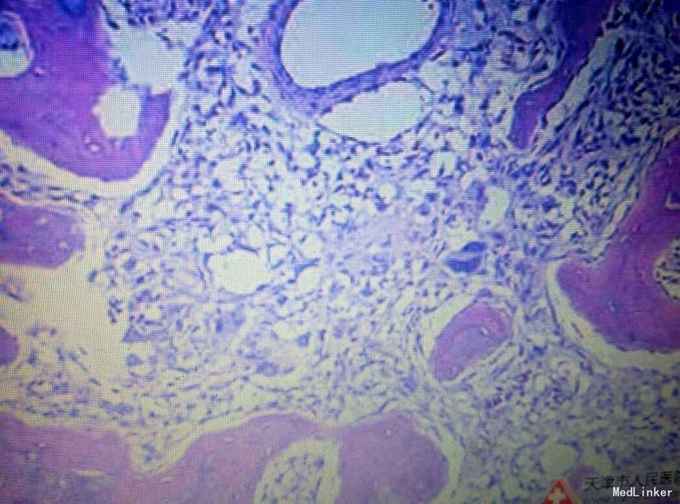

诊断:左乳癌?左乳纤维腺瘤?肉瘤? 治疗:患者入院后于局麻下行左乳肿物穿刺活检术,术后病理提示:左乳恶性肿瘤,肉瘤待排,遂全麻下行左乳癌改良根治术加腋窝淋巴结清扫术,术后病理示:左乳恶性肿瘤,考虑骨肉瘤可能性大,淋巴结未见转移。

随访与讨论:说实话,在之前根本没听说过有这一个疾病,这次也是长了见识,不过完全靠的是病理科。查文献可知:原发性乳腺骨肉瘤是一种比较罕见的恶性肿瘤, WHO乳腺肿瘤学分类将其归于间叶性肿瘤,是骨外骨肉瘤的一种。在原发乳腺恶性肿瘤中发病率低于0.1%,好发于中老年女性,主要通过血道转移,最常累及肺脏,几乎无淋巴结转移。该病诊断主要依赖于病理结果。由于该病恶性程度高,对放化疗均不敏感,目前尚缺乏统一的治疗方案。所以我们也只是做了改良根治术,后期化疗综合医生决定以及患者意愿综合实施,当然全身评估是必不可少的。